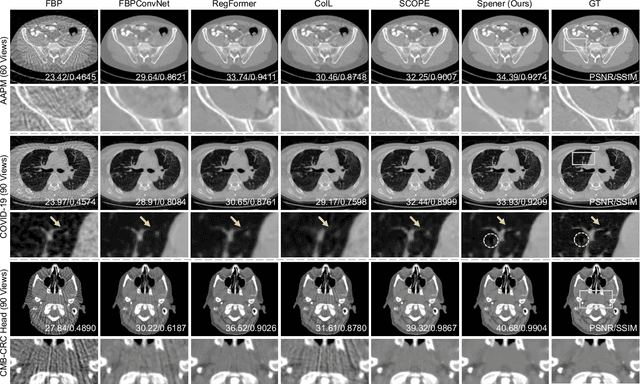

Abstract:Emerging unsupervised implicit neural representation (INR) methods, such as NeRP, NeAT, and SCOPE, have shown great potential to address sparse-view computed tomography (SVCT) inverse problems. Although these INR-based methods perform well in relatively dense SVCT reconstructions, they struggle to achieve comparable performance to supervised methods in sparser SVCT scenarios. They are prone to being affected by noise, limiting their applicability in real clinical settings. Additionally, current methods have not fully explored the use of image domain priors for solving SVCsT inverse problems. In this work, we demonstrate that imperfect reconstruction results can provide effective image domain priors for INRs to enhance performance. To leverage this, we introduce Self-prior embedding neural representation (Spener), a novel unsupervised method for SVCT reconstruction that integrates iterative reconstruction algorithms. During each iteration, Spener extracts local image prior features from the previous iteration and embeds them to constrain the solution space. Experimental results on multiple CT datasets show that our unsupervised Spener method achieves performance comparable to supervised state-of-the-art (SOTA) methods on in-domain data while outperforming them on out-of-domain datasets. Moreover, Spener significantly improves the performance of INR-based methods in handling SVCT with noisy sinograms. Our code is available at https://github.com/MeijiTian/Spener.